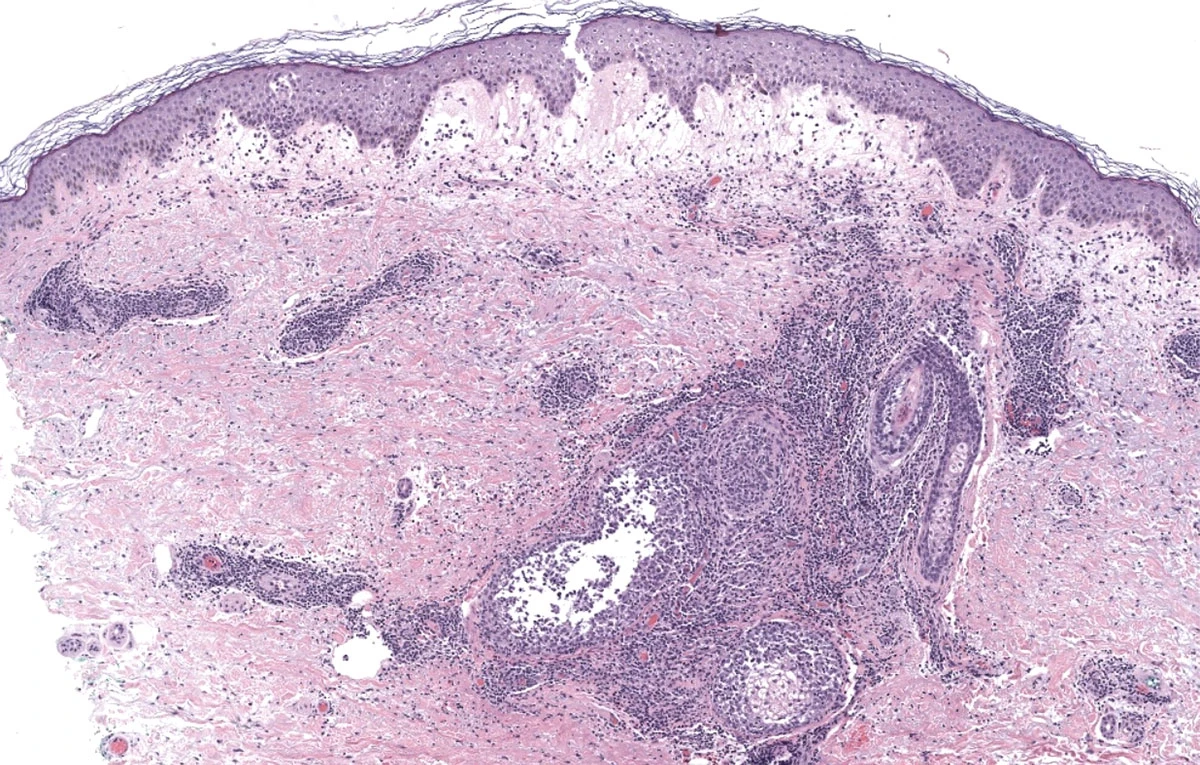

- Módulo 5: Dermatitis ampollosas

- Módulo 7: Patrón nodular/difuso